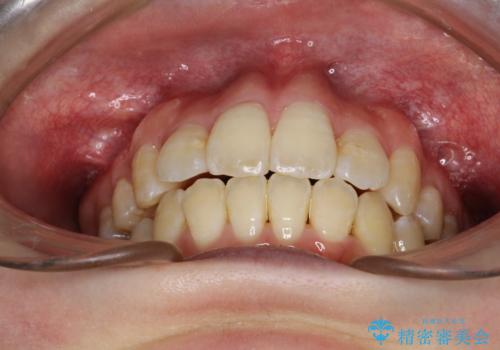

重度のガタガタ ワイヤーによる抜歯矯正

抜歯したスペースを使うことで、ガタガタと出っ歯を改善することができました。